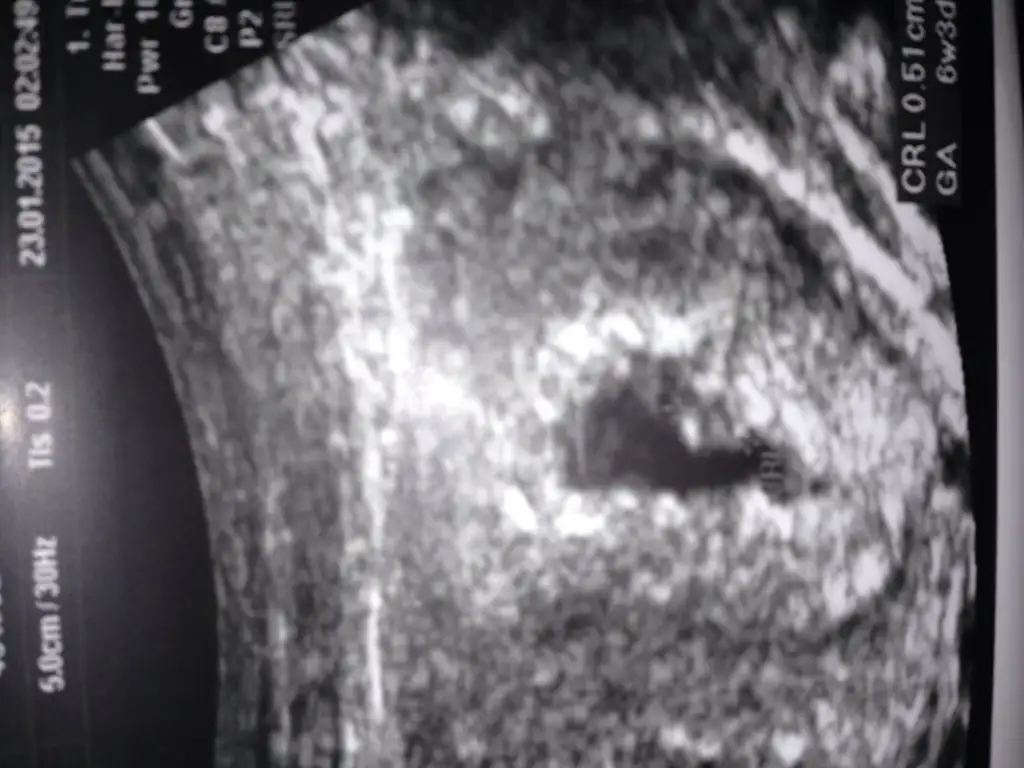

alttakinde sağda olduğu belli ama üsttekinin sanki erken görüntü olmuş şu an solda bence oğlan geliyorKızlar alttaki kızımın 7 haftalık, üstteki de bugün çekildi 7 haftalık, sizce ne şimdiki

Yarın kendi Dr uma gîdicem yine koyarım, hem bî günde ne kadar değişiyo görmüş oluruzalttakinde sağda olduğu belli ama üsttekinin sanki erken görüntü olmuş şu an solda bence oğlan geliyor

Cnm bebek solda derken kar ında mı solda, onun bi anlamı yok sanırım.benin anladığım 7. Hafta ultrasonunda kesenin içindeki bebek karından bakıldığında soldaysa erkek, sağdaysa kız. Benim kızımda tuttu bakalım bunda tutacak mıDediğin gibi olabilir ama karın ultrasonunda da ters görünmüyor mu ve çıktıya göre yorum yapılmıyor mu? benim bebiş sol tarafta ultrasonu hep sola koyuyoruz ama kağıtta sağda gözüküyor.